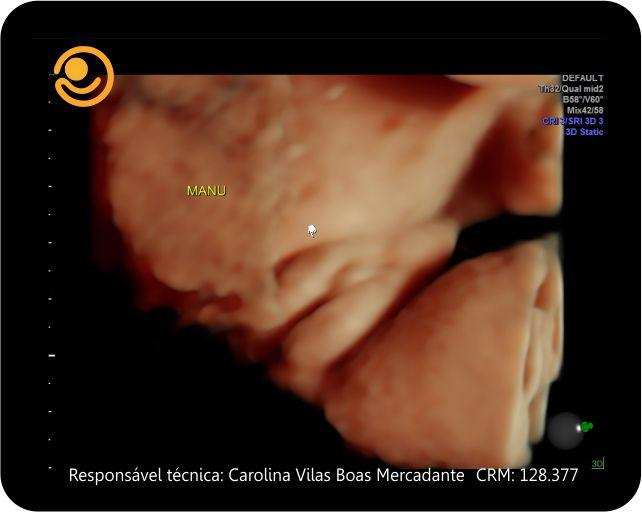

Imagens 3D / 4D

✓ Ultrassonografia 3D/ 4D com imagem em HD